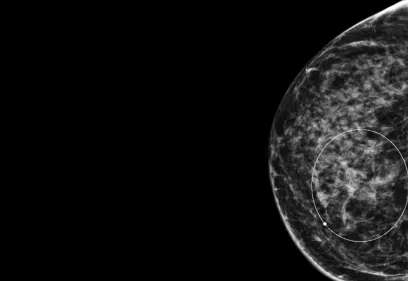

Cover image of a body scan of IMAGES magazine

IMAGES

Images is an annual publication on milestones and progress in radiology.

Read the latest issue